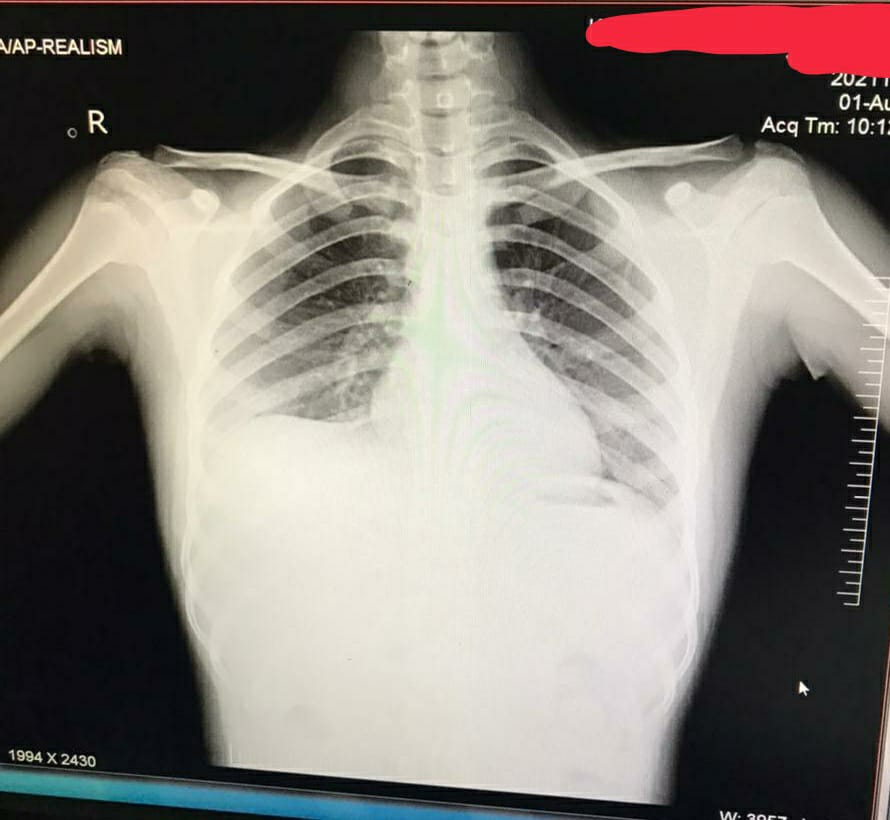

CHEST X-RAY